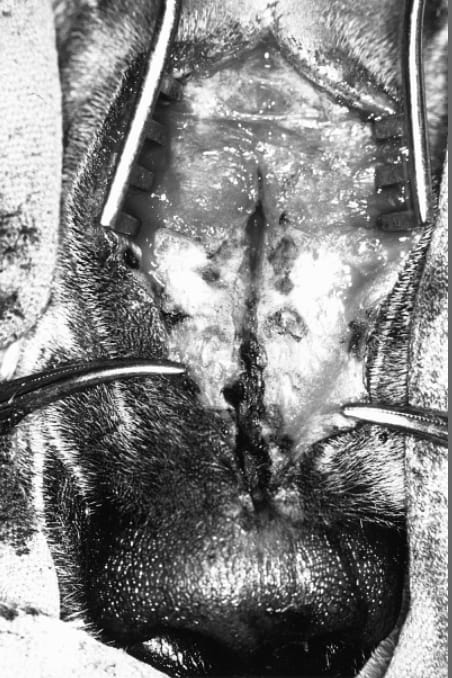

Intraoperative view (dog 3). The tract has been exposed by a dorsal median incision. The pigmented epithelial tissue of the tract is seen extending caudally, penetrating into the nasal septum, one third of the way along the nose.